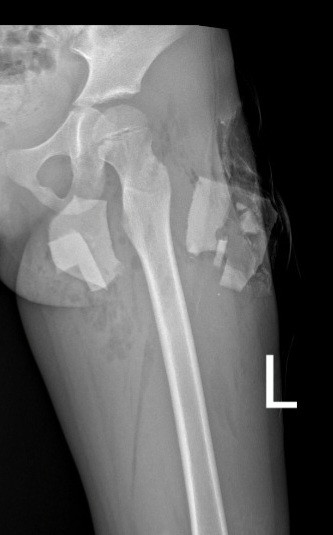

Ngay sau khi vào viện, bệnh nhân được khám, sơ cứu băng bó cầm máu vết thương và chụp phim X-quang. Phim chụp phát hiện có đa dị vật cản quang đầu trên đùi trái và cẳng chân phải. Bệnh nhân được chỉ định phẫu thuật cấp cứu, xử trí vết thương lấy dị vật.

Quá trình mổ, các bác sĩ phát hiện dị vật là mảnh sành xuyên từ mặt ngoài đùi trái, đi giữa lớp cơ thẳng đùi vào đến vùng dưới bẹn nơi có bó mạch thần kinh đi qua. Dị vật gãy làm đôi, một mảnh ở phía ngoài vết thương, còn một mảnh nằm sâu bên trong, để lại đường hầm nằm dưới lớp cơ.

Đặc biệt mảnh dị vật ở phía trong nằm sát ngay bên cạnh bó mạch thần kinh đùi, nhưng chưa gây tổn thương đến bó mạch. Tuy nhiên, việc gắp dị vật ra để không ảnh hưởng đến mạch máu thần kinh của bệnh nhân là điều không hề dễ dàng.

| Dị vật đâm sâu vào đùi trẻ. Ảnh: Bệnh viện Sản nhi Nghệ An. |